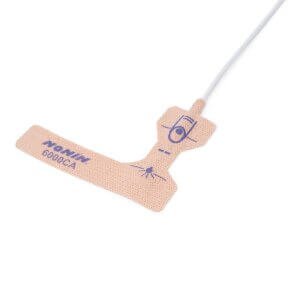

- Easy to Use Illustrated finger guide ensures easy and accurate placement by caregiver or patient

- Special Adhesive Allows the sensor to be repositioned multiple times as needed